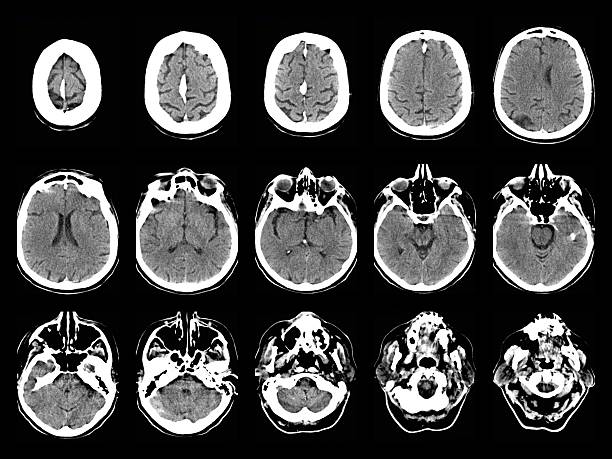

老年神經(jīng)系統會(huì )出現哪些問(wèn)題?

老年神經(jīng)系統疾病給全球醫療保健系統帶來(lái)了沉重的負擔。閱讀文章了解更多信息。

世界人口正在老齡化,老年人的數量正在增加。隨著(zhù)預期壽命的延長(cháng),老年人患神經(jīng)系統疾病的幾率也在上升。了解和解決這些問(wèn)題對于為老齡人口提供適當的醫療保健和支持至關(guān)重要。老年神經(jīng)系統疾病給全球醫療保健系統帶來(lái)了沉重的負擔。這些疾病通常需要長(cháng)期護理、專(zhuān)業(yè)醫療服務(wù)和持續管理。通過(guò)有效解決和治療神經(jīng)系統問(wèn)題,可以?xún)?yōu)化醫療保健資源以滿(mǎn)足老年人的需求。

神經(jīng)系統疾病,也稱(chēng)為神經(jīng)系統疾病或病癥,是影響中樞神經(jīng)系統(大腦和脊髓)、周?chē)窠?jīng)系統(大腦和脊髓以外的神經(jīng))或兩者的疾病。這些疾病是由神經(jīng)系統的結構、功能或化學(xué)異?;蚬δ苷系K引起的。

神經(jīng)系統疾病有多種病因,包括遺傳因素、發(fā)育問(wèn)題、感染、免疫系統疾病、退化過(guò)程、腫瘤、創(chuàng )傷和其他潛在健康狀況。它們會(huì )影響任何年齡段的人,從出生到老年。

神經(jīng)系統問(wèn)題會(huì )嚴重影響老年人的生活質(zhì)量。阿爾茨海默病、帕金森病和癡呆癥等疾病會(huì )導致認知能力下降、記憶力喪失、功能障礙以及日?;顒?dòng)依賴(lài)他人。有效管理這些疾病對于老年人保持獨立和幸福至關(guān)重要。